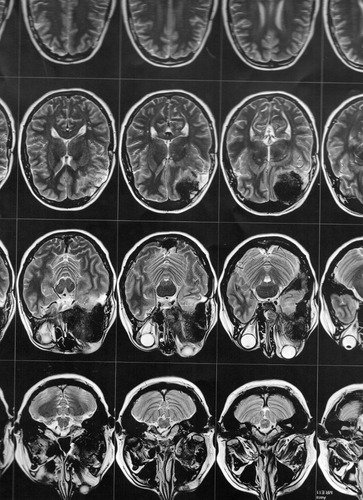

Então este médico solicitou exames de imagem (ressonância magnética e tomografia) para avaliar a situação, os quais foi constatado que o meningioma ainda está ali, e que continua empurrando o olho e se expandindo para outras áreas. Trata-se de um meningioma gigante (medindo 6 x 6,6 x 6 cm), que está localizado na placa do assoalho da fossa média e anterior.